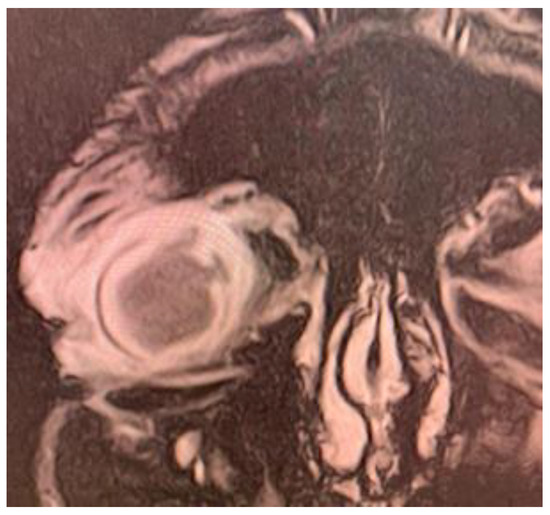

Ultrabiomicroscopy (UBM) confirmed posterior irido- lenticular synechiae on 360⁰ and thickening of the ciliary body (Figure 1). Ocular ultrasound exam revealed total retinal detachment, multiple fine vitreous echoes suggestive for vitritis, homogeneous thickening of the choroid and a 3mm diameter hyperechogenic mass invading sclera (Figure 2). A differential diagnosis between an extrascleral extension of an endophthalmitis and a possible intraocular tumor with scleral penetration was considered.

Figure 2.

Ocular ultrasonography (mode A/B): total retinal detachment, retinal and choroidal thickening; multiple densities in the vitreous body suggestive for vitritis; in the superior sector, a hypodense mass with loss of scleral echo and deformed ocular contour.